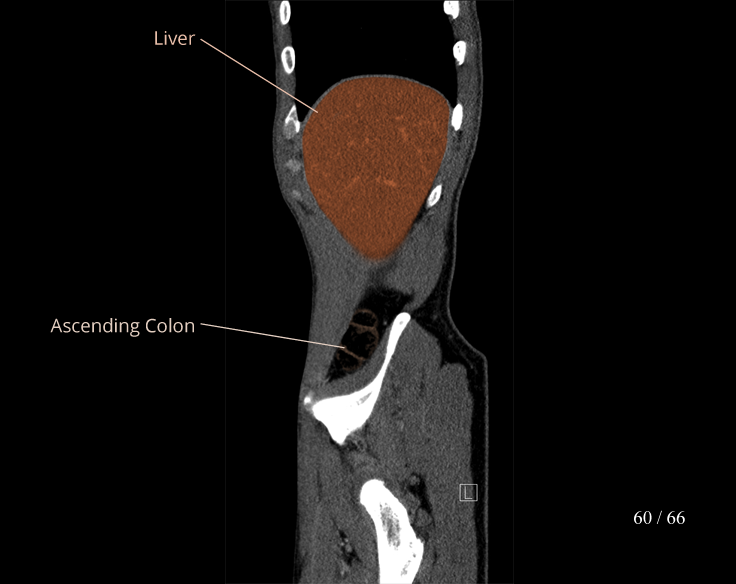

Body

Covers abdominal CT anatomy.